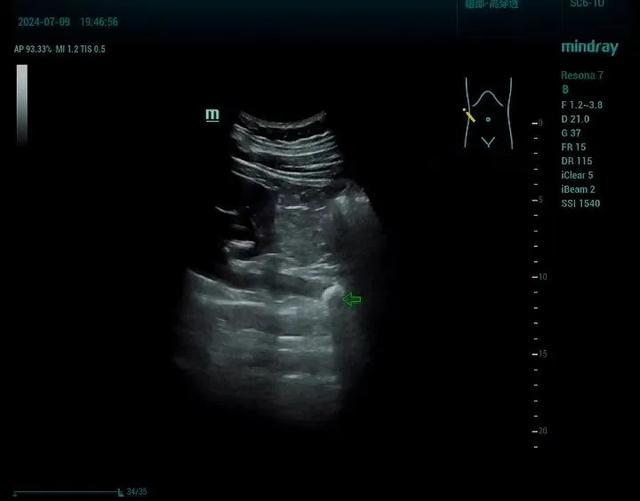

五、首选检查方式

泌尿系超声:无创、快捷,既能显示结石,又能定位梗阻部位,还能判断积水程度及肾脏实质改变。